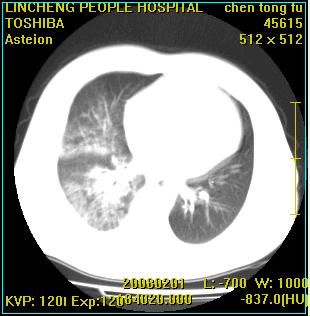

患者,男性,62岁。主因头晕,发热,咳嗽6天,高热达39度,esr19mm/h,wbc 3.9×10 9/l

实变区见空气支气管征,支气管通畅,考虑为大叶性肺炎,右侧少量胸水

考虑为右肺大叶性肺炎伴少量胸腔积液,建议复查,如病变不吸收或吸收不明显,建议纤维支气管镜检查,除外细支气管肺泡癌的可能。

考虑感染性病变,不除外细支气管肺泡癌建议:1、治疗后复查。2、作支纤镜检查。

实变区见空气支气管征,支气管通畅,考虑为大叶性肺炎,右侧少量胸水。